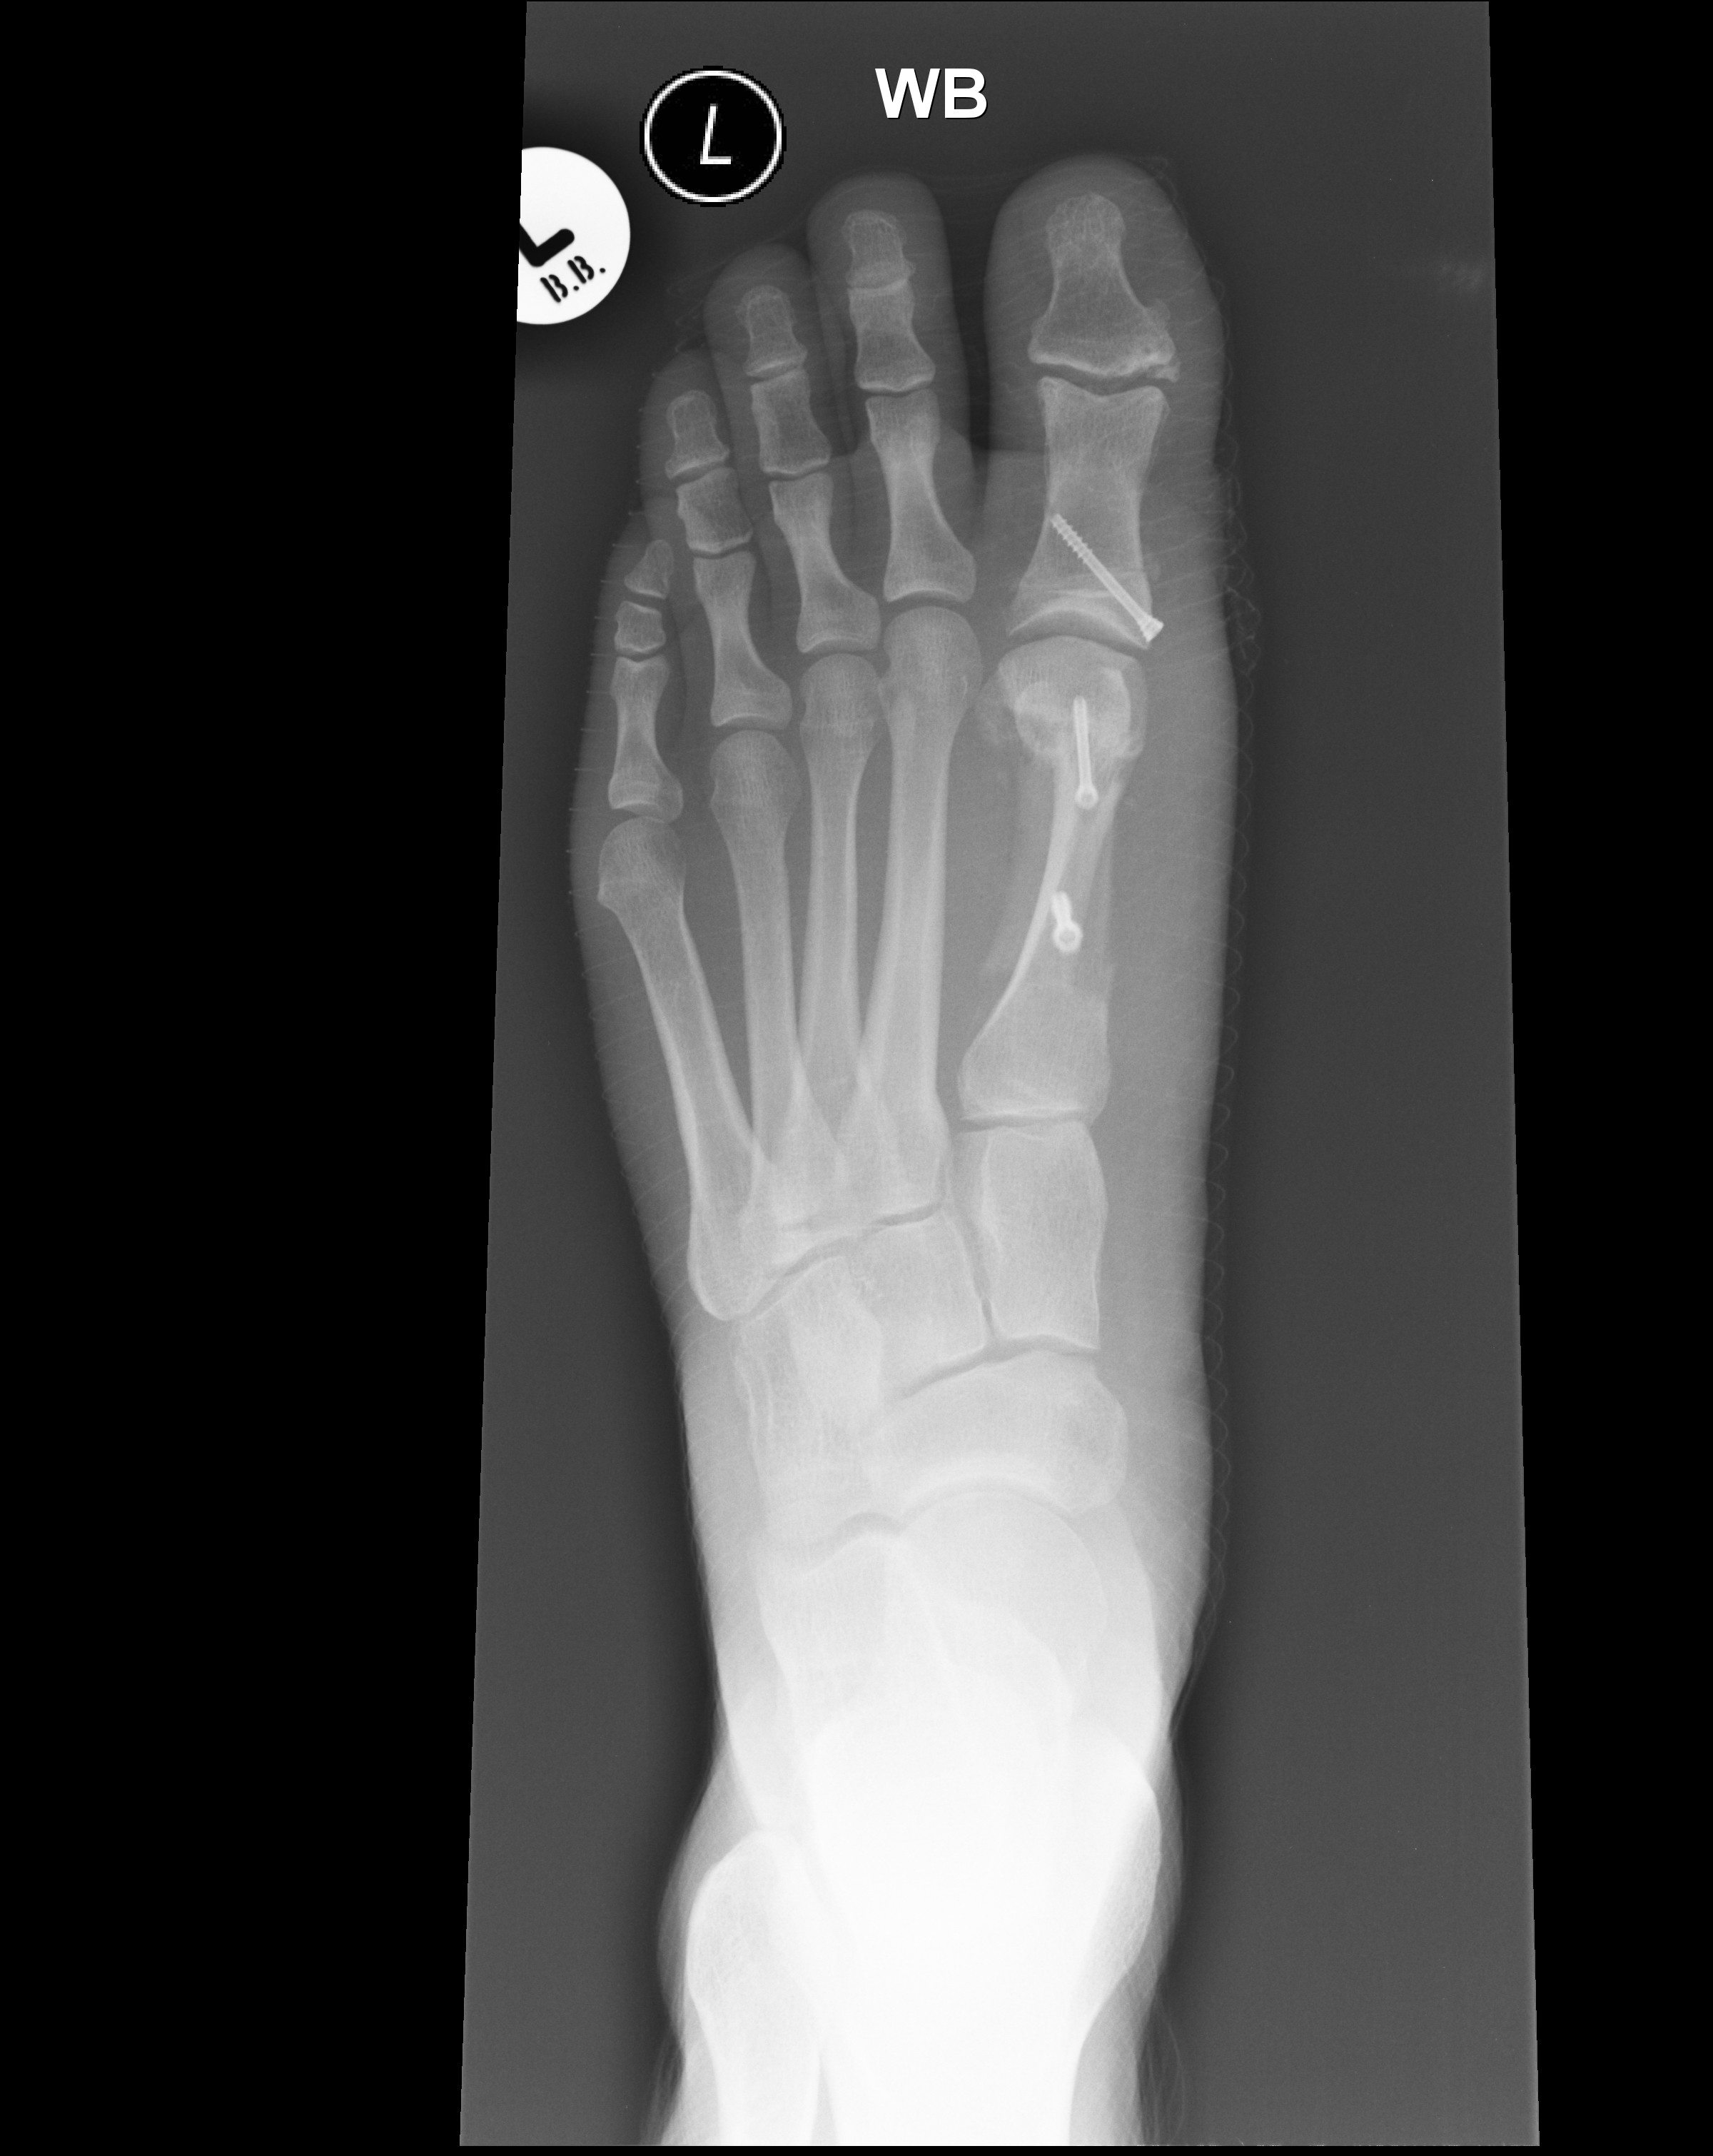

Well I made it back to London this week and back to work on Monday. The foot is on the mend and I have now progressed to the B3 Cbt Engr post final exercise hobble! All of my x-rays have now come back fine and I am now encouraged to walk but it is still a bit uncomfortable. It takes me twice as long to get to work as I have to walk slowly to the bus stop and site office but hopefully it will be back to whacky races on the bike again soon. At least my foot looks like a good bit of engineering now with it’s 3 titanium bolts!